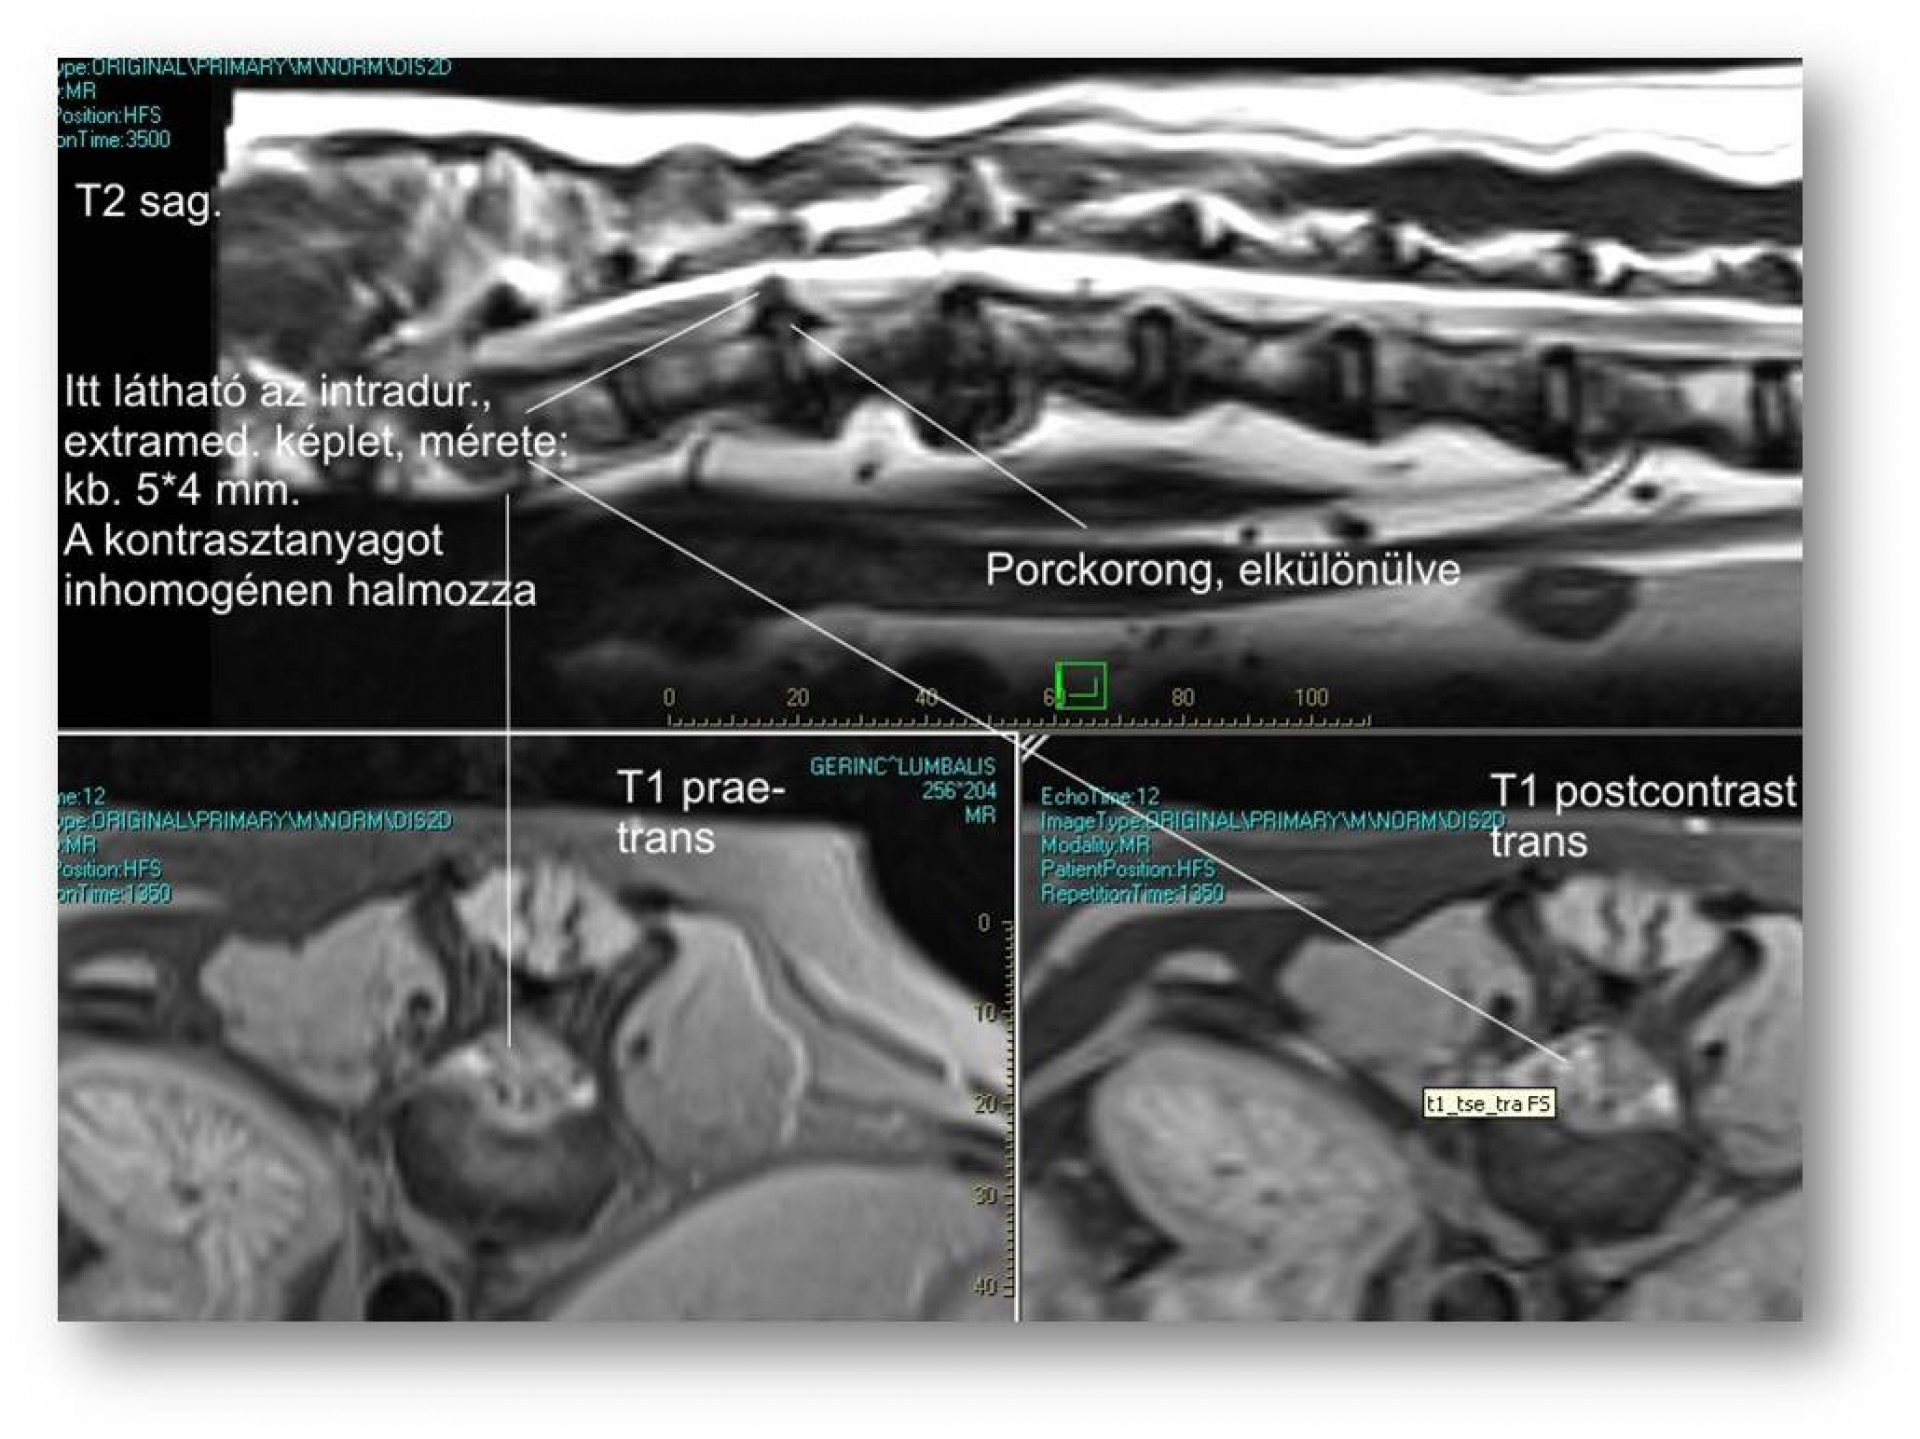

Ám az öröm nem tartott sokáig. Szürke Farkas 5 nappal a műtéte után a kocsiba ugrás közben felsírt és mire a rendelőbe ért a fájdalomtól fel sem tudott állni. A kórházi felvételt követően fájdalomcsillapítók, antibiotikumok adását kezdtük meg és mivel a műtéti területen klinikai és RTG vizsgálattal sem találtunk a fájdalmat magyarázó elváltozást Kaposvárra, MRI vizsgálatra vittük. 2 nappal később meglepődve olvastuk az eredményt: a 9.-10.( Th9-Th10 ) hátcsigolyák valamint a 7 ágyéki és az 1. keresztcsonti csigolyák ( L7-S1 ) közötti porckorong gyulladásos elváltozása ( ld.: discospondylitis ) mellett a 11. és a 12. hátcsigolya magasságában ( Th 11-Th12 ) a gerincvelőt összenyomó daganatos elváltozás volt látható. Mivel a porckorongok gyulladása megmagyarázta a gerinctájéki fájdalmasságot, annak kezelése és a fájdalom további csillapítása volt az első teendőnk. Néhány nappal a fájdalom enyhülését követően a gerincvelőt összenyomó daganatot műtétileg eltávolítottuk. Ezt követően Szürke Farkas még további 60 napot töltött a kórházban. A lábadozása napról napra szépen alakult. Betegségének 90. napján hazaadtuk és a gyógyszerek további adása mellett állapotát hetente ellenőriztük.